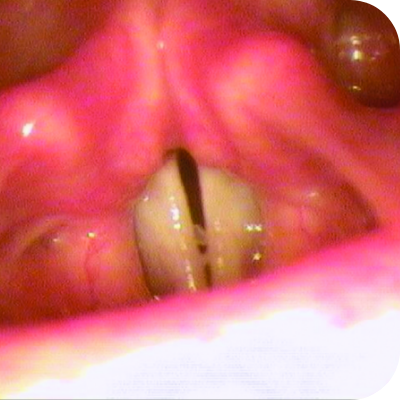

Ligneous gingivitis with gum swelling and lesions

Ligneous gingivitis in a real patient with PLGD-14

32% of people with PLGD-1 experience gingival involvement6†

Ligneous gingivitis is typically painless but can lead to periodontal destruction (tissue loss) and ultimately tooth loss if left untreated.3

Ligneous gingivitis caused by congenital plasminogen deficiency type 1, manifesting as gum lesions Respiratory tract lesions in plasminogen deficiency type 1 patient Skin lesions on arm

Real patients with PLGD-14,11

Lesions due to PLGD-1 may present in a variety of ways, from watery, stringy pseudomembranes to thick wood-like lesions.3